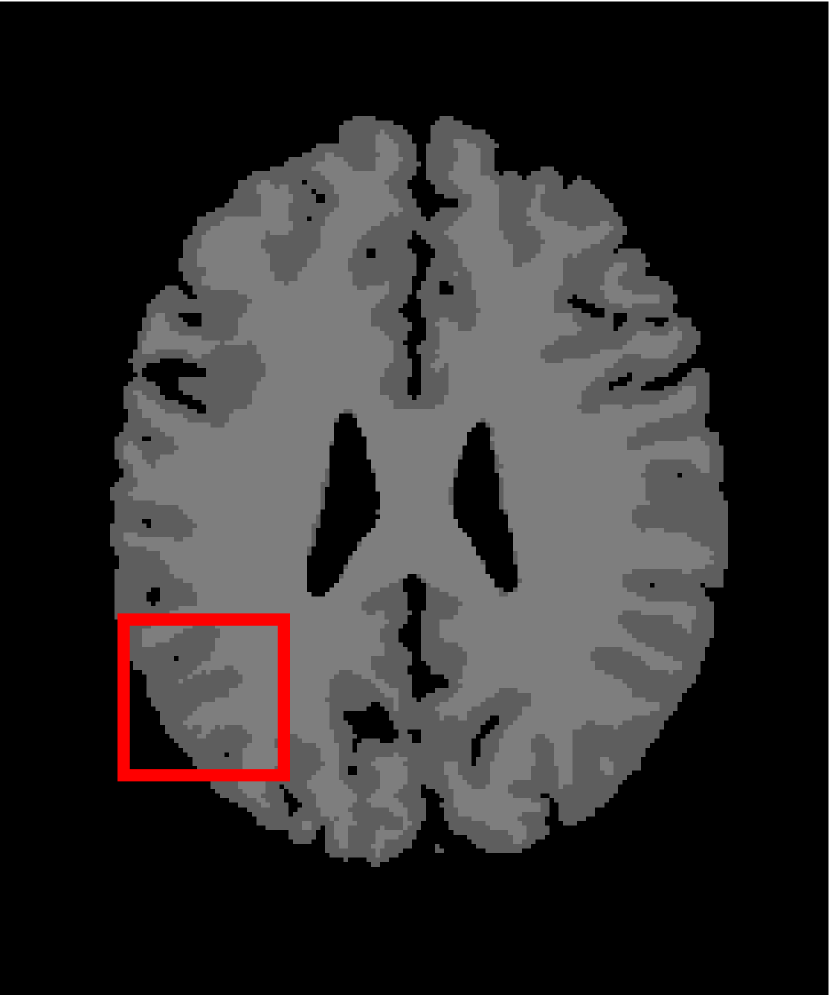

In the second experiments, we segment two medical images coming from a simulated brain database (BrianWeb): http://www.bic.mni.mcgill.ca/brainweb/. The two images are generated by T1 modality with slice thickness of 1mm resolution, 9% noise and 20% intensity non-uniformity. Here, the two images are represented two slices in the axial plane with the sequence of 100 and 110. Moreover, there are golden standard segmentations in the dataset. We set the numbers of clusters to 4. The visual comparisons are illustrated in Figs. 6 and 7.

By focusing on the marked red square in Figs. 6 and 7, we easily find that FCM_S1, FCM_S2, FGFCM and ARKFCM are sensitive to noise. FLICM and KWFLICM are vulnerable to severe intensity inhomogeneity. FRFCM brings overly smooth results due to the use of gray level histograms. WFCM and DSFCM_N cause several contours to change. However, LRFCM acquires clear contours and suppresses noise adequately. Moreover, we find that the segmentation result of LRFCM is closer to ground truth.